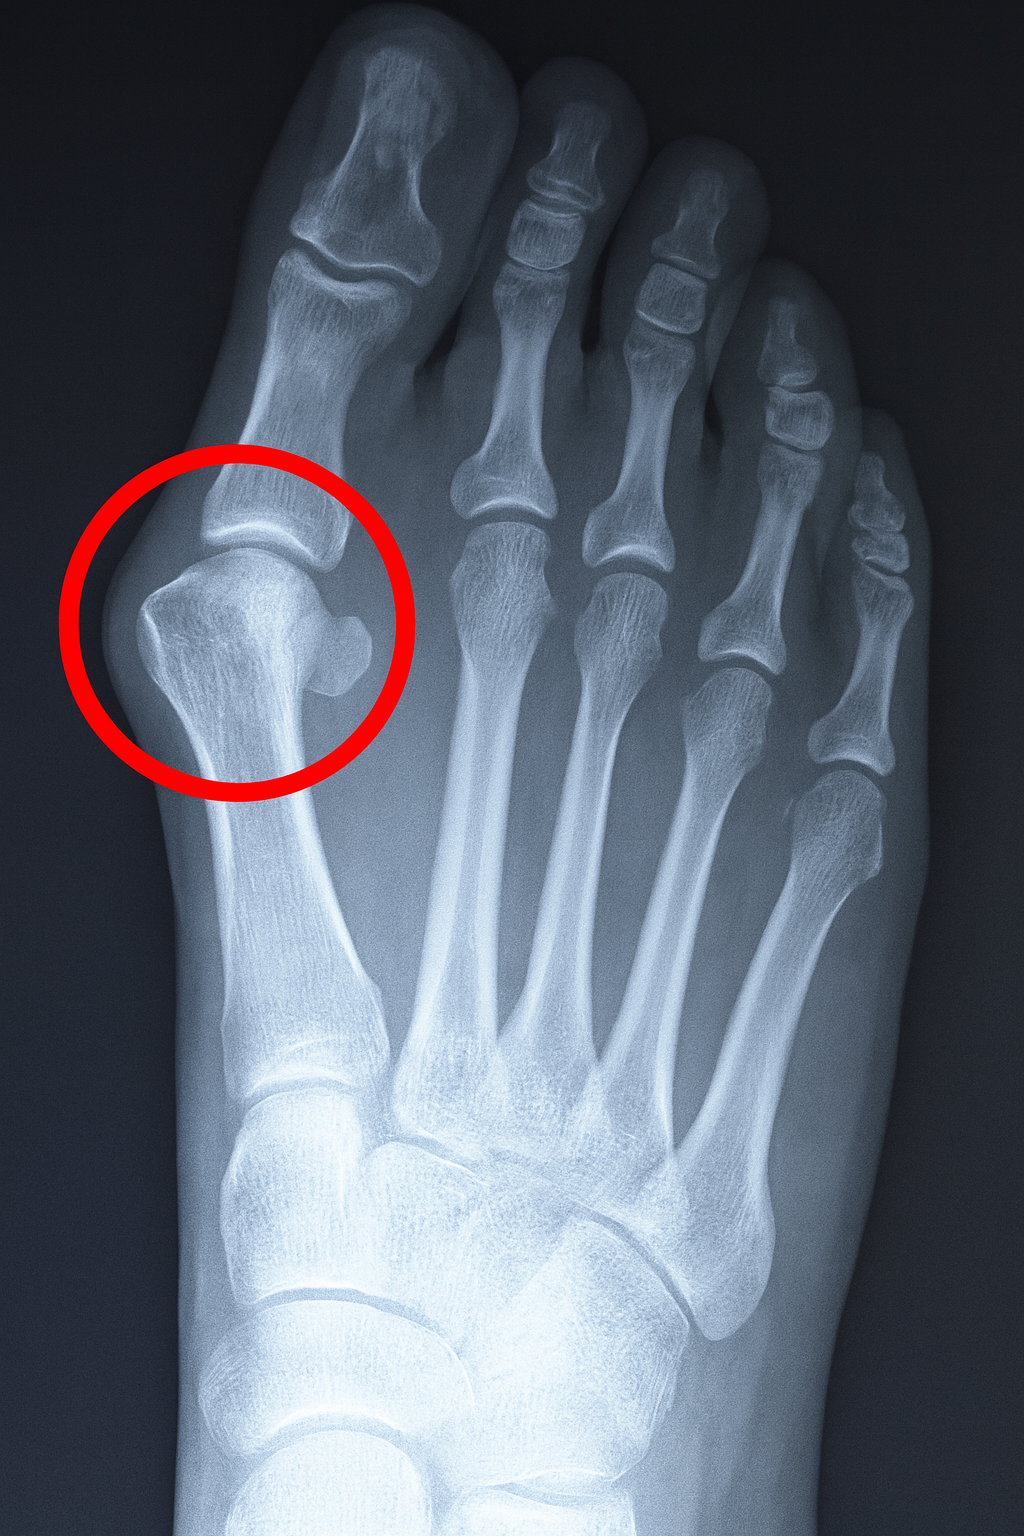

BunionA bunion is a growth resulting from an enlargement of the joint at the side of the big toe. Bunions are formed when the big toe is bent inwards and a bony lump forms on the outside of the joint. Over time, the lump becomes larger and the bunion can become painful. As a result, arthritis and stiffness can often develop. Additionally, this condition can worsen when callous and corns develop on the bunion.

While the term bunion refers to the enlarged joint, Hallux valgus is a Latin term that refers to the deviation of the big toe that results from this enlargement.

Bunion X-RayBunions: Common Causes